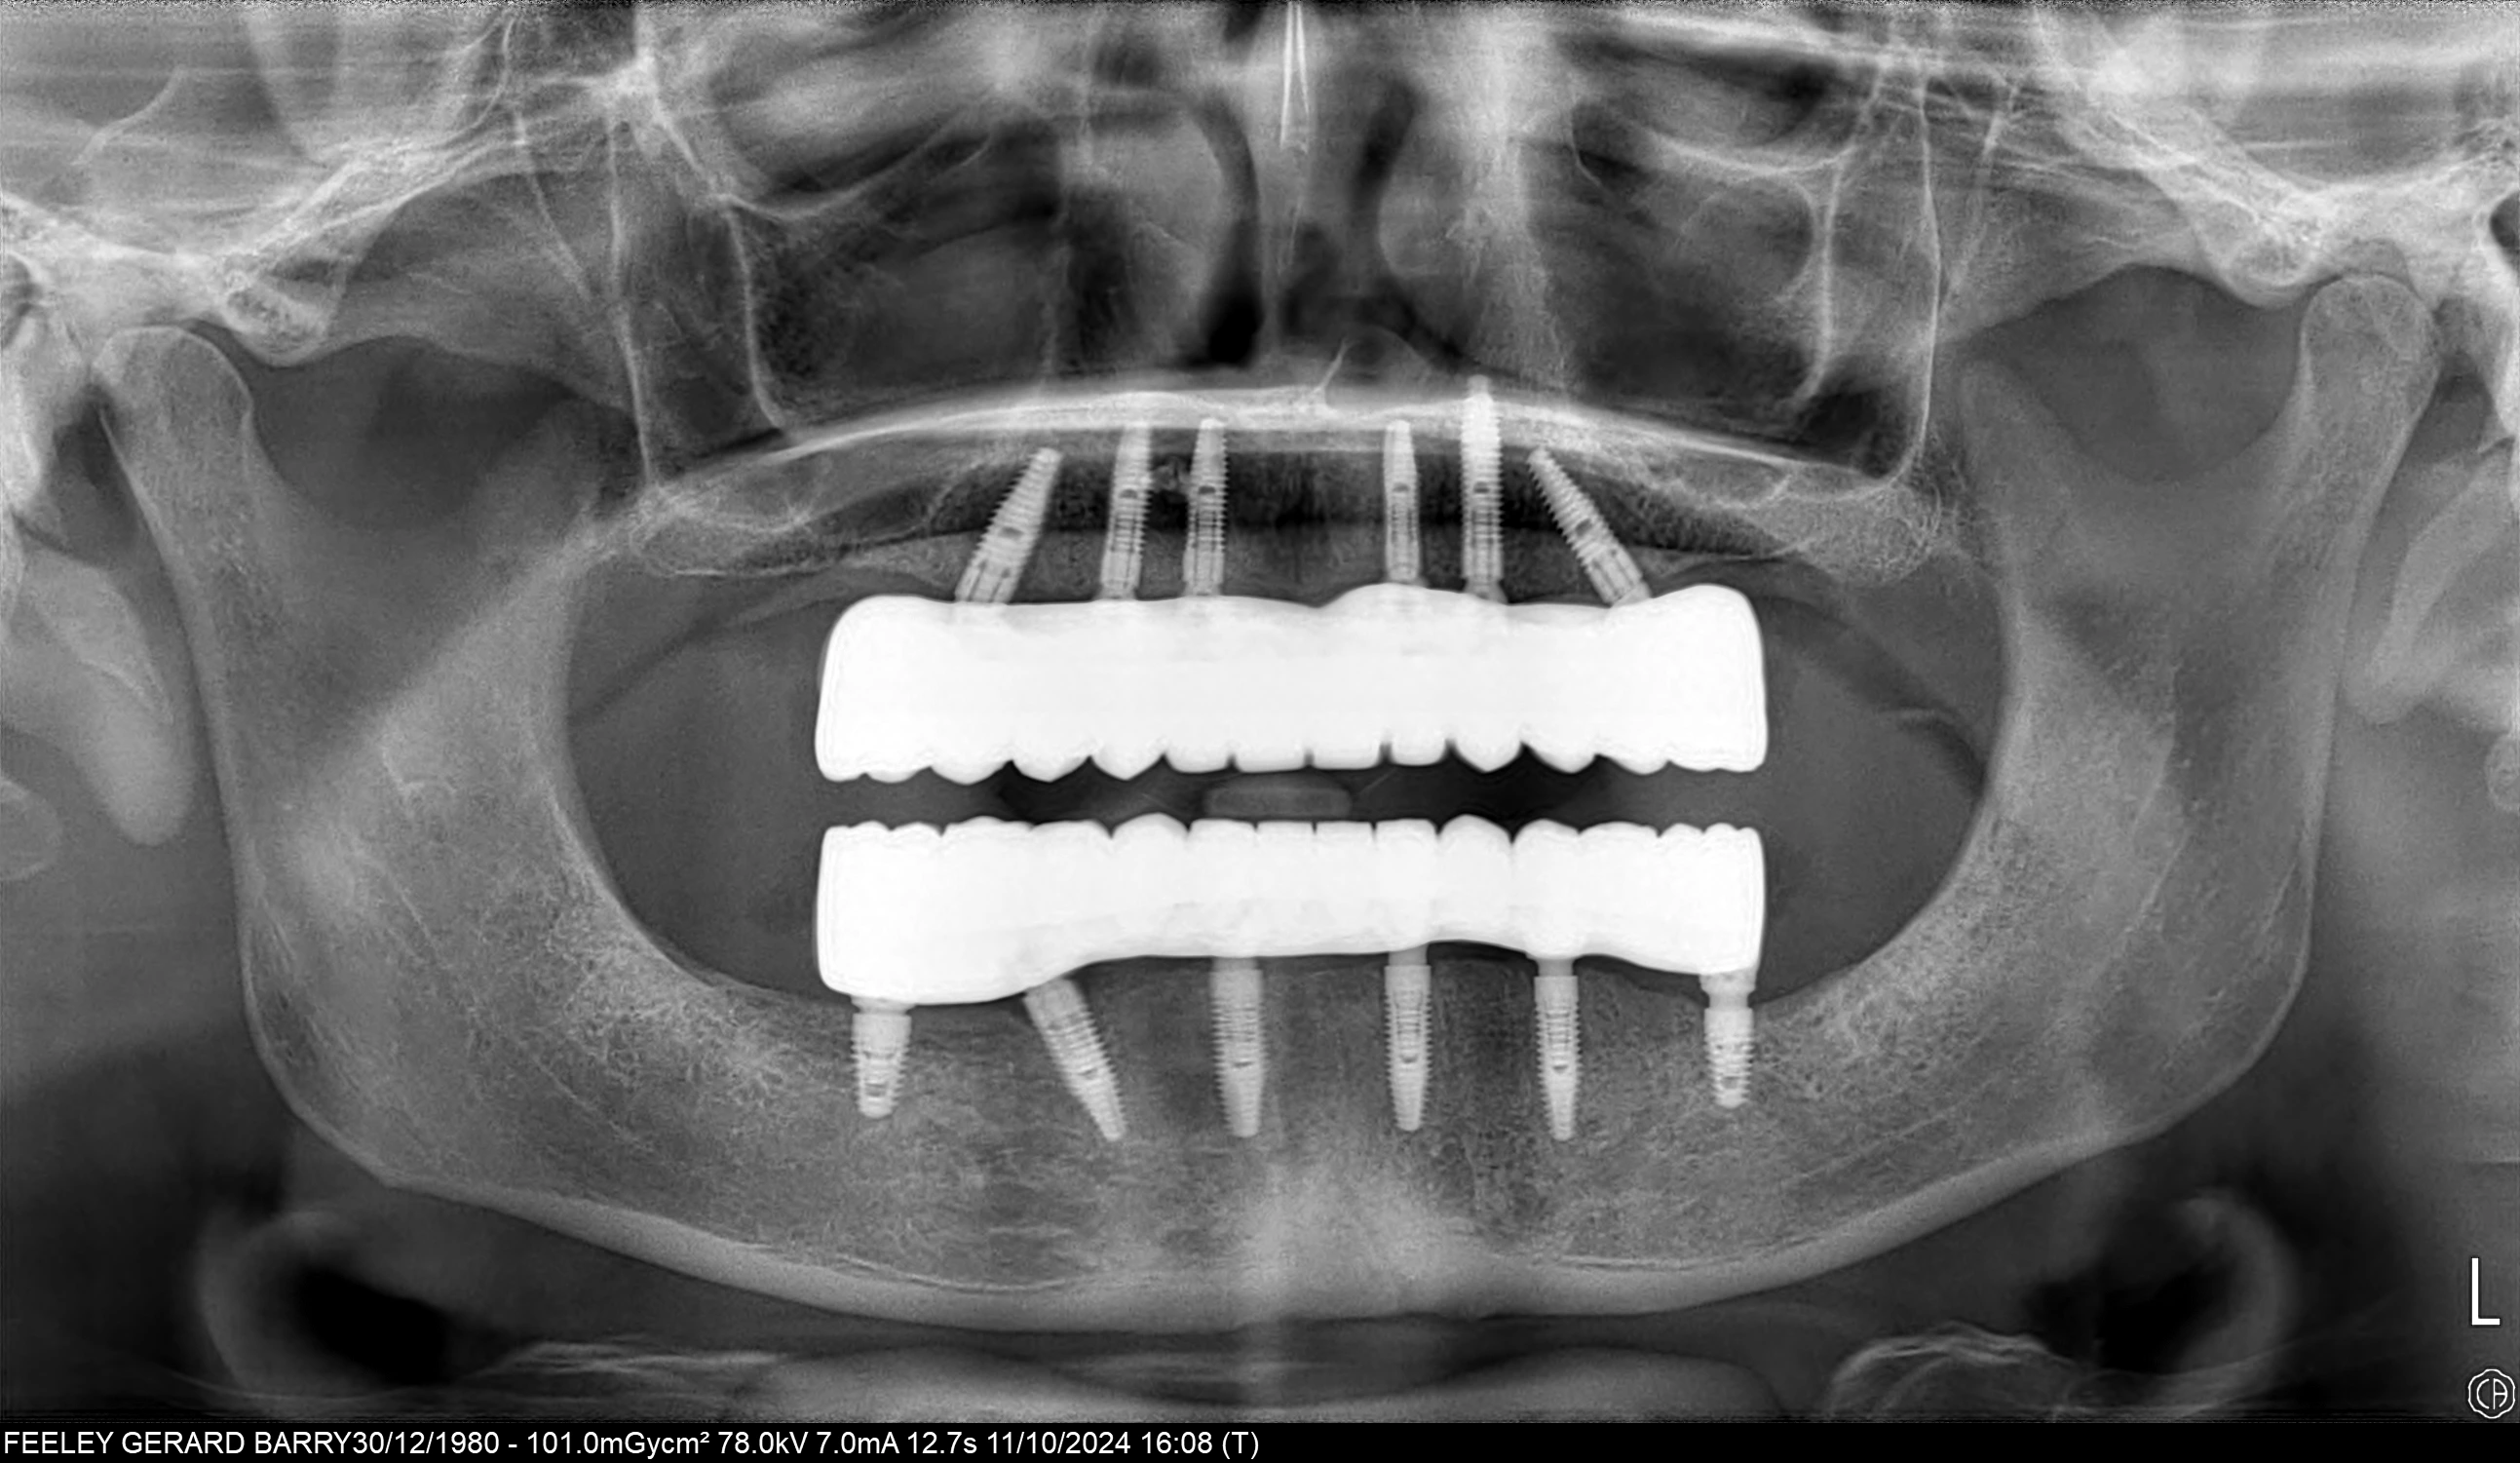

Unlike traditional removable dentures, All-on-6 implants are fixed, meaning they do not slip or shift. They offer the feel and function of natural teeth, allowing you to eat, speak, and smile with confidence. Additionally, implants help preserve jawbone density, preventing bone loss and maintaining facial structure over time. With their natural aesthetics, long-lasting durability, and high patient satisfaction, All-on-6 implants are a transformative solution to restore both the function and beauty of your smile.

At Attelia, our All-on-6 restorations are supported by a titanium frame that provides superior durability and ensures chewing forces are distributed equally across all six implants. This enhances patient comfort and guarantees long-term success. To increase precision and functionality, we use multi-unit abutments on each implant, ensuring optimum angles, alignment, and a more natural bite.

All-on-6 provides better stability, stronger biting force, and more even load distribution by using six implants per jaw instead of four. The use of multi-unit abutments and titanium frameworks further improves alignment and long-term success, making All-on-6 ideal for patients seeking maximum support and durability.